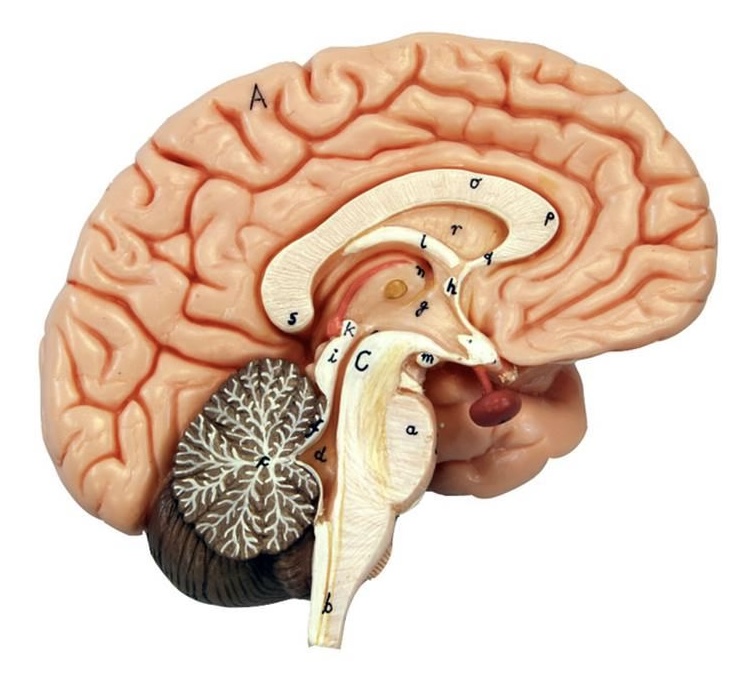

What is D?

lateral ventricle

Imagine thin membrane separating the 2 lateral ventricles

septum pellucidum

What is C?

3rd ventricle

What is B?

cerebral aqueduct

What is A?

4th ventricle

What is below A at the very end?

central canal (spinal cord)

What is C?

midbrain

tectum (corpora quadrigemina): superior colliculus

tectum (corpora quadrigemina): inferior colliculus

What is a?

pons

medulla oblongata

intermediate mass of thalamus

hypothalamus

What is the pink bulb?

pineal gland

corpus callosum

fornix

What is A?

cerebral cortex

cerebral tracts

cerebral hemispheres

longitudinal fissure

What are these ridges?

gyri

What are these shallow grooves?

sulci

Divides parietal from frontal lobe

central sulcus

precentral gyrus

postcentral gyrus